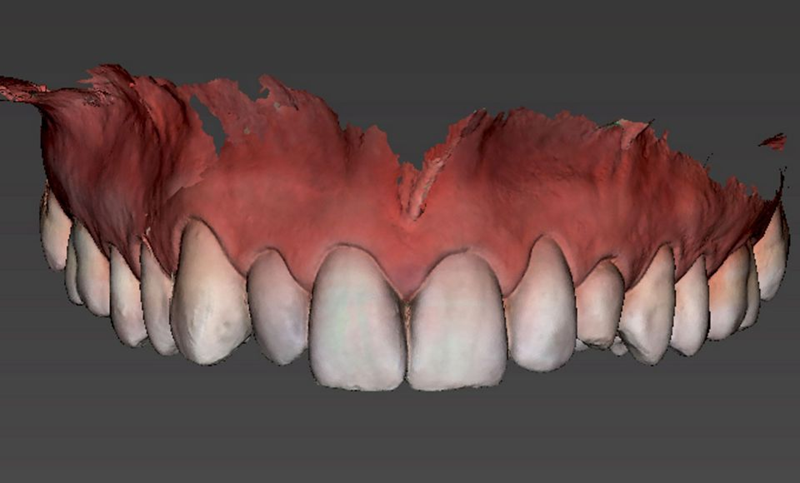

3. 在 coDiagnostiX® 规划软件中处理 Dicom(CBCT 检查)和 STL(光学印模和数字蜡型)数据,以便仔细规划种植体植入并设计手术导板。 (图18-19)。

Fig.18: Planning the case step-by-step with coDiagnostiX®.

Fig 19: Planning the surgical guide.

4.通过coDiagnostiX®计划生产印刷手术导板和树脂模型(图20-21)。